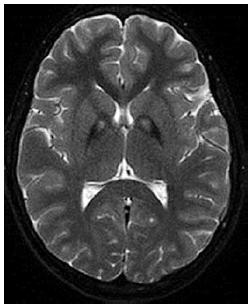

Menino de 10 anos de idade apresenta história progressiva de distonia, disartria e regressão cognitiva. A ressonância magnética de crânio revela o seguinte achado na imagem.

Qual o gene mais provavelmente associado ao quadro?